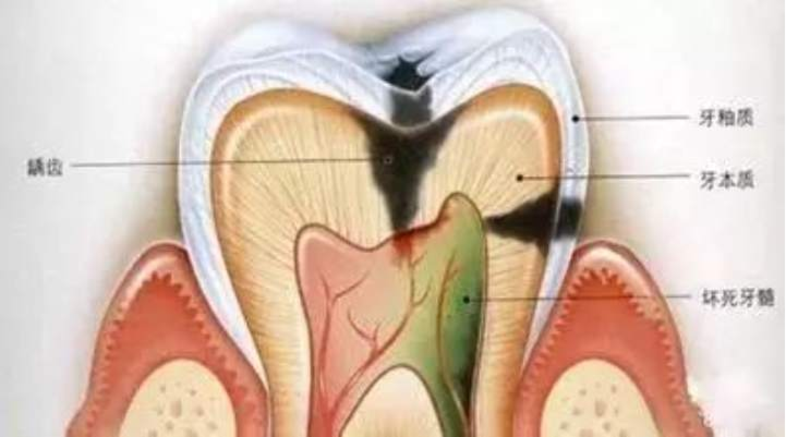

牙齿分为三层,最外层坚硬的牙釉质,不会感觉到疼痛;中间的牙本质能够感受到疼痛;最里层是敏感的牙神经,一受刺激便会疼痛难忍。

牙髓炎:细菌进入牙神经,患者会有剧烈的疼痛感。如果不及时治疗,细菌会杀死牙神经

运气不好的话,它可能是这样子的↓↓

龋病可发展为牙髓炎、根尖周炎,引起剧烈疼痛,严重者还可造成间隙感染